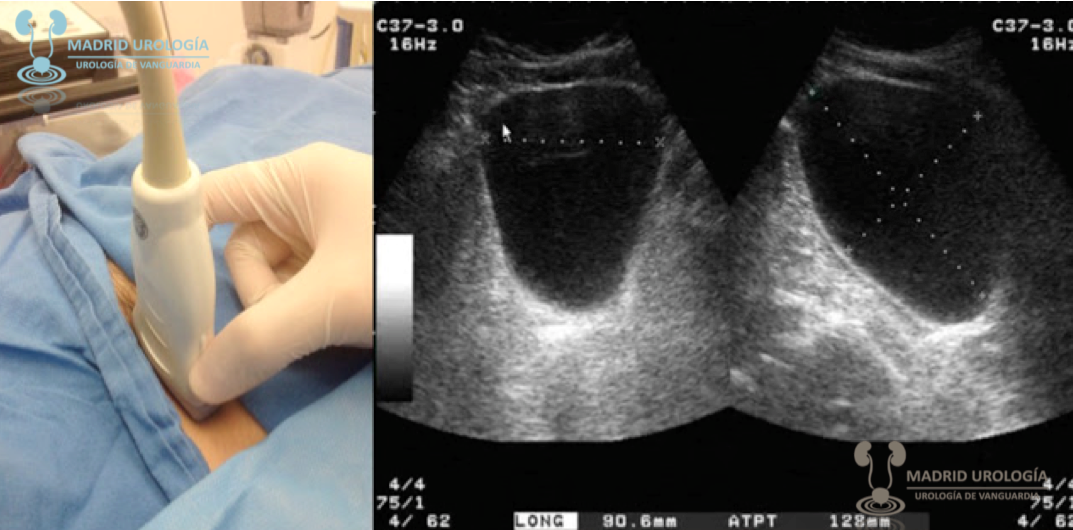

ULTRASONOGRAFIA

Menos invasivo, se puede realizar en embarazadas, no utiliza medio de contraste. Es operador dependiente, y tiene limitaciones anatomicas (pacientes obesos). Se descirben como hipereocioc, anecoico, hipoecoico. Es un examen de rutina y tamizaje: determina variaciones antomicas, lesiones  del parenquima renal, litisis mayor 4mm, aproximacion incial de uropatia obstructiva alta, y el doppler evlau vascularizacion, calidad de flujo y perfusion. Los calculos producen sombra acustica VIA URINARIA SUPERIOR manejo y diagnostico incial de masas renales, ademas se puede guiar biopsias, derivaciones urinarias (nefrostomia).

VIA URINARIA INFERIOR La prostat normal tiene volumen de 20ml, luego de los 40 años por aumento de sensibilizacion a la testosterona empieza a crecer, y ese creimiento puede hacer que el vaciado de la orina sea inadecuado. La ecografia sirve para estudio incial de patologia prostatica. Sirve para ver vejiga, prostata, vesiculas seminales y uretra. Debe infromar pared de la vejiga, engrosamiento parietal, contenido anecoico, estudio funcional (perm,ite ver llenado, vaciado y predecir volumen). El tamaño de la prostat es de acuerdo al diametro longitudinal ( distancia entre el cuello y apex de la prostata) Sirve de apoyo a intervenciones, punciones percutaneas, cistostomia percutanea o guiada por eco, biopsia prostatica., biospia vesical. PATOLOGIA GENITAL Fracturas de pene, detectar la solucion de conitnuidad de la albuginea, signo de la berenjena. Alteraciones en la abugnea del cuerpo cavernoso, como placas fibroticas que encurva el pene, enfermedad de Peyronie. Secuestros vasculres, he,agiomas como causas de disfuncion erectil conestudio eco doppler, Diagnostico incidental y carcterizacion de masas testiculares. direnciando patolopgia escrotal benigna (quiste epididimo), versus aumento de voluemn escrotal com hidrocele o lesioones intraparenquimatosas del testiculo.  La torsion testicular hay alteracion en el doppler, el que requiere pabellon inmediato. Si es un tumor, realizar orquiectomia. En la torsion se ve en la ecografia el signo del tornado.